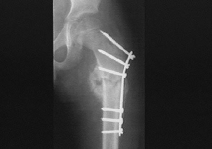

Операция: 18.10.2011. Закрытая репозиция, интрамедуллярный МОС с блокированием перелома правого бедра с рассверливанием костномозгового канала.

Рентгенограмма правого бедра в передней и боковой проекции от 19.10.2011

На рентгенограмме правого коленного сустава в двух проекциях дистальное блокирование перелома правой бедренной кости при интрамедуллярном металлоостеосинтезе осуществлена 2 винтами. Снимки выполнены с ротацией коленного сустава ЭЭД= 0,003. На ренгенограммах черепа и скуловых костей определяется оскольчатый перелом правой скуловой кости. Фиксация осуществлена 1 спицей Киршнера. Смещение отломков сохраняется. Стояние их удовлетворительное. ЭЭД=0,091.

Оперативное лечение. Наиболее распространённым методом оперативного лечения перелома диафиза бедра является интрамедуллярный остеосинтез металлическим штифтом. При этом чаще пользуются ретроградным методом его введения. Другим методом является экстрамедуллярный остеосинтез массивными компрессирующими пластинами.

При данном типе травмы изначально методом лечения использовалось скелетное вытяжение, затем было произведено оперативное лечение: закрытая репозиция, интрамедуллярный МОС с блокированием перелома правого бедра с рассверливанием костномозгового канала.